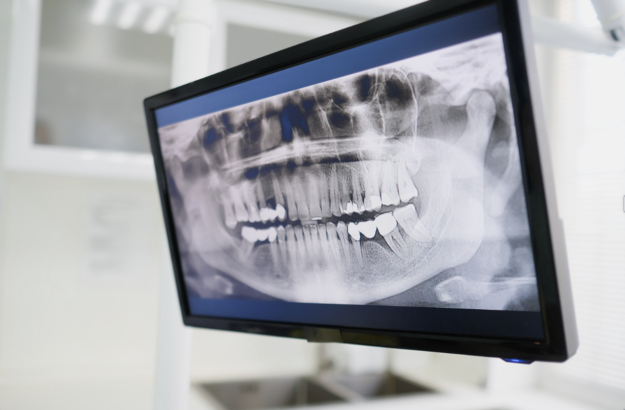

当院では、CT検査などを用いて骨の状態を詳細に確認し、治療の可否を慎重に判断します。

当院では、インプラント治療を行う前に、CT検査などを用いて骨の状態を詳細に確認します。